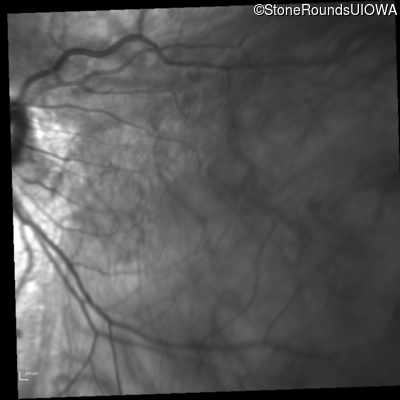

Infrared Fundus Photograph - Right - 20/40 +2

Exemplar